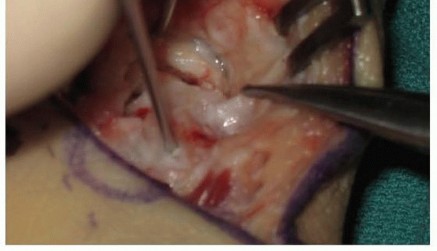

Attention is then turned to the distal radius for graft harvest. Through the proximal extent of our existing incision, the pronator quadratus is elevated off the volar aspect of the distal radius. A cortical window is mapped out based on the caliper measurements. Using an oscillating saw and fine osteotomes, a corticocancellous wedge is carefully harvested. The surgeon must ensure the structural integrity of the cortical face of the graft while capturing a robust volume of underlying cancellous bone.

The harvested graft is meticulously shaped on the back table using a rongeur or a fine burr to perfectly match the dimensions of the scaphoid defect. The graft is then press-fit into the volar void with the cortical surface facing volarly to act as a structural buttress, and the cancellous portion facing the medullary canal to promote osteogenesis. The joysticks are relaxed, allowing the native ligamentous tension to compress the scaphoid fragments against the newly inserted wedge graft, locking it securely in place.